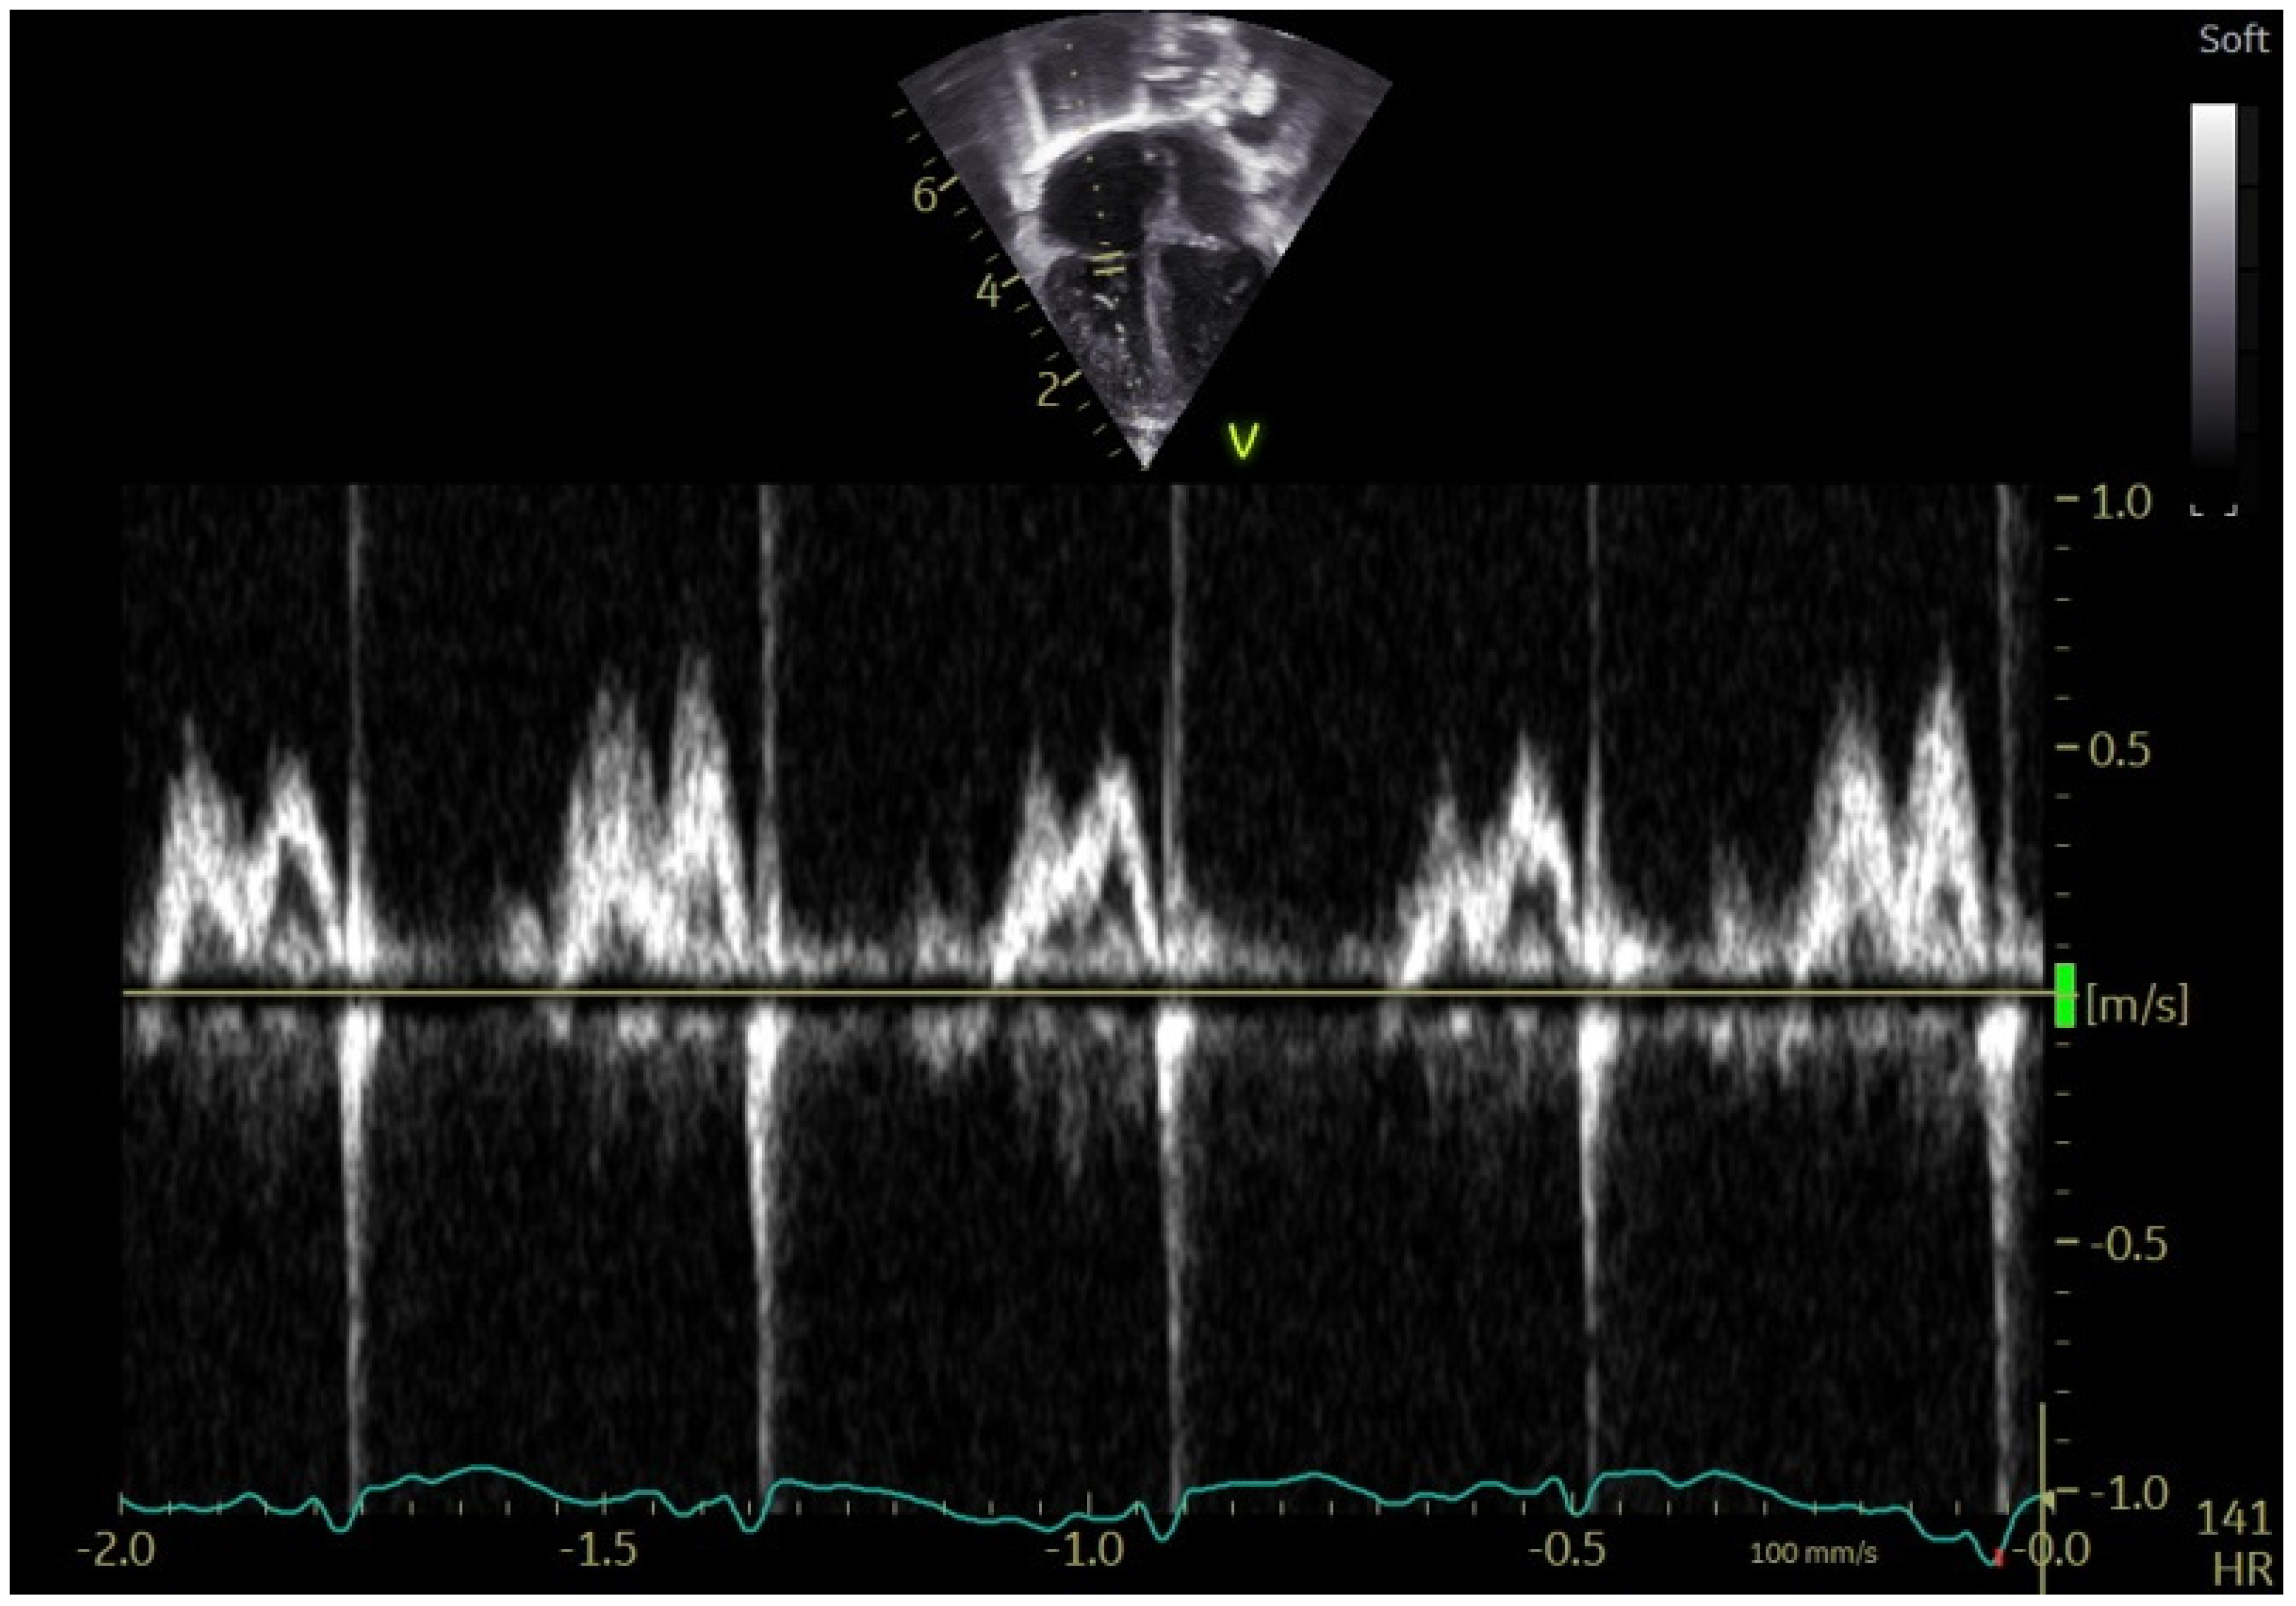

3.3. Patterns of TV Inflow in Children with CHD

- Cantinotti, M.; Marchese, P.; Scalese, M.; Franchi, E.; Assanta, N.; Koestenberger, M.; Van den Eynde, J.; Kutty, S.; Giordano, R. Normal Values and Patterns of Normality and Physiological Variability of Mitral and Tricuspid Inflow Pulsed Doppler in Healthy Children. Healthcare 2022, 10, 355. [Google Scholar] [CrossRef]

- Cantinotti, M.; Lopez, L. Nomograms for Blood Flow and Tissue Doppler Velocities to Evaluate Diastolic Function in Children: A Critical Review. J. Am. Soc. Echocardiogr. 2013, 26, 126–141. [Google Scholar] [CrossRef]

- Harada, K.; Takahashi, Y.; Shiota, T.; Suzuki, T.; Tamura, M.; Ito, T.; Takada, G. Effect of Heart Rate on Left Ventricular Diastolic Filling Patterns Assessed by Doppler Echocardiography in Normal Infants. Am. J. Cardiol. 1995, 76, 634–636. [Google Scholar] [CrossRef]